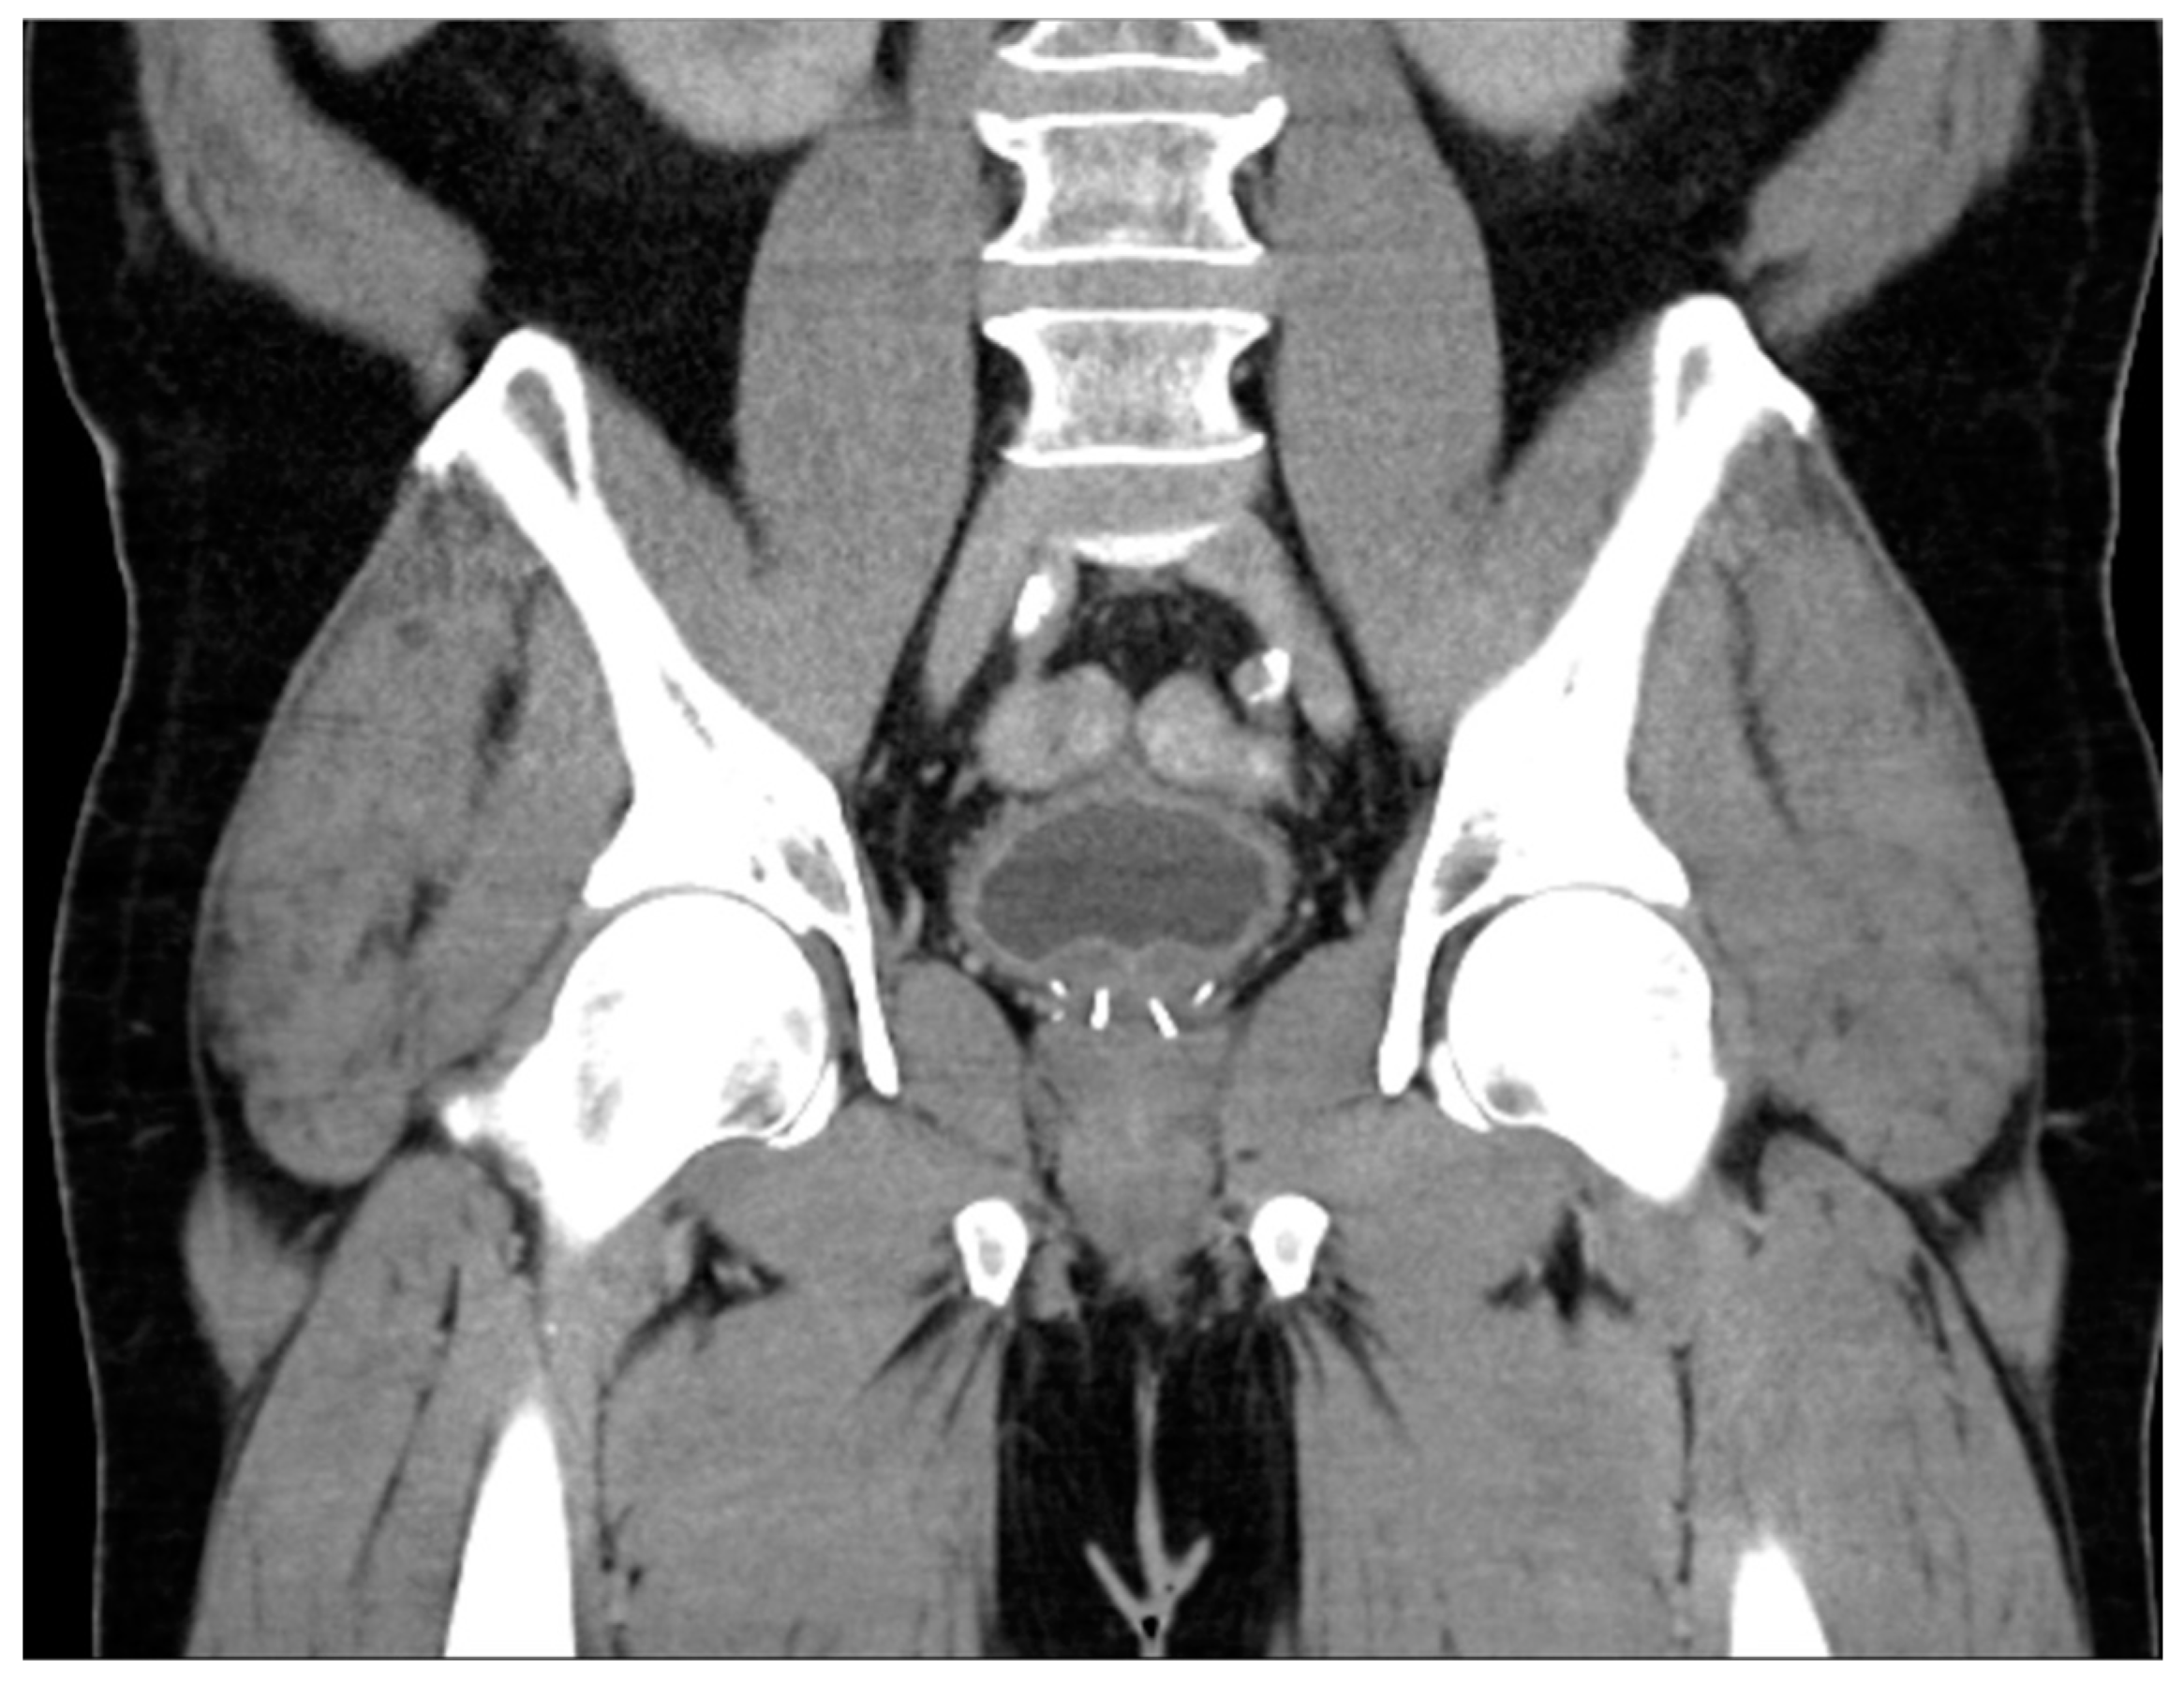

Figure 7. Coronal CT appearance of UroLift device indicated by linear densities within the bilateral prostate gland.

The prostatic urethral lift (PUL), commonly referred to as UroLift, is a clip delivery system that involves the placement of clips under cystoscopic vision that retracts obstructing prostatic tissue. Importantly, the AUA guidelines suggest candidates for this method should not have an obstructive middle lobe, which is easily identifiable in most imaging modalities. The advantages of PUL include the ability to perform in an office without the use of general anesthesia, as well as the preservation of tissue, which provides patients with a higher likelihood of preserving erectile and ejaculatory function [72]. Upon imaging, PUL has an appearance similar to brachytherapy seeds, but there will not be as many present, and they will be confined to the central prostate (Figure 7).